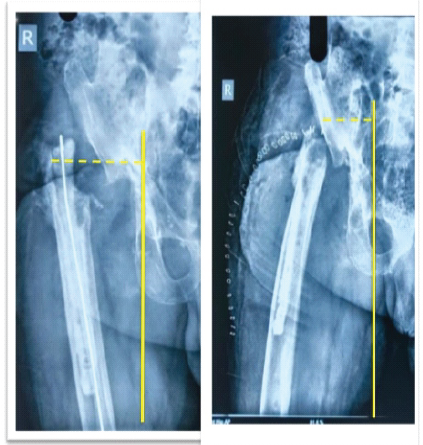

X-rays of the pelvis with both hips-anteroposterior view (Fig. 1) showed proximal and lateral migration of the proximal femur on the right side with an antibiotic nail in situ. A computed tomography (CT) scan was done to delineate the anatomy of the acetabulum and femur (Fig. 2).

Figure 1: Pre-operative X-ray pelvis with both hips – anteroposterior view.

On post-operative radiograph, we drew a line from the tear drop to the proximal-most aspect of the femur and compared it with the pre-operative radiograph showing medialization and distalization of the proximal femur as compared to the pre-operative status (Figs. 6 and 7).

Figure 6, 7: Comparison of pre-operative and post-operative radiographs showing medialization of the proximal femur.